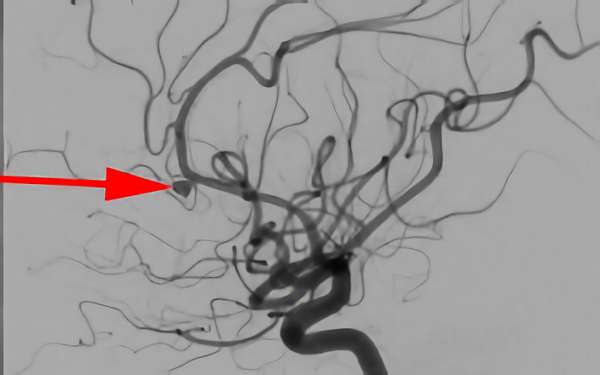

No.1631 手術後